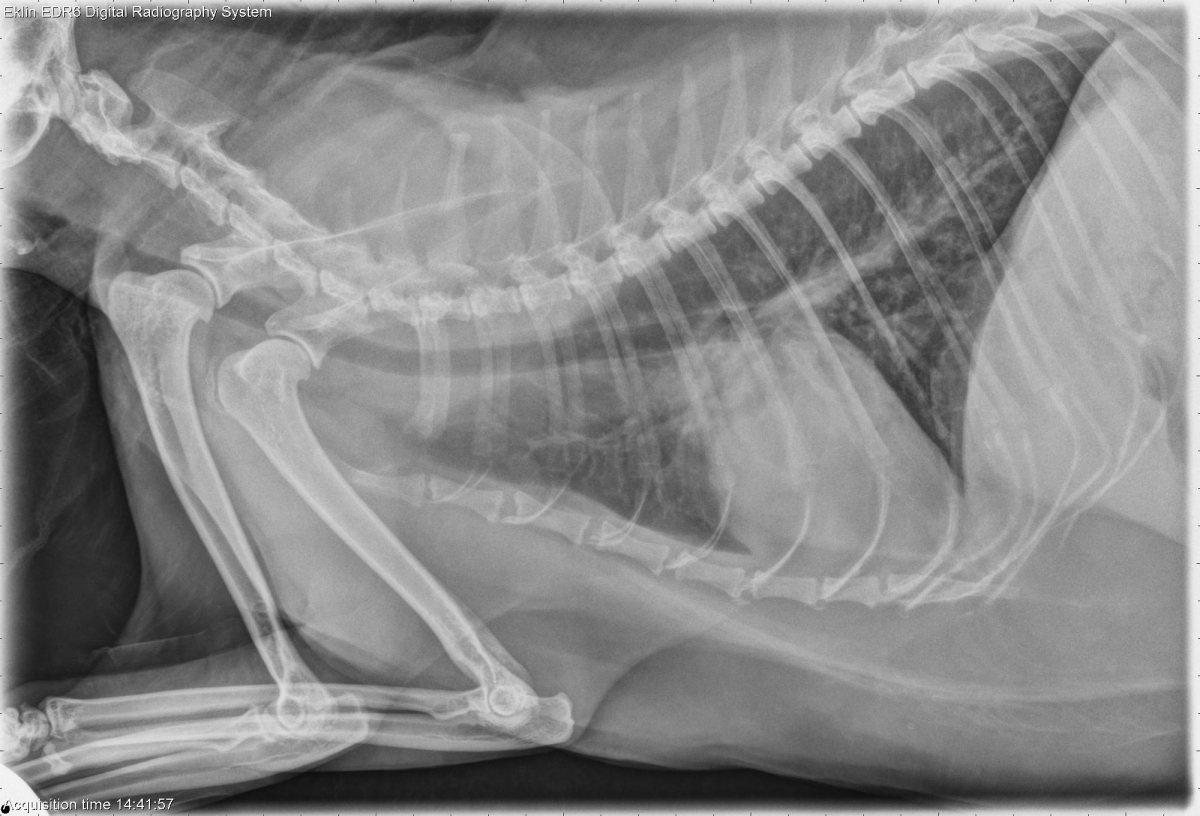

Today’s case is a 14 year old male neutered Maine Coon cat with coughing episodes. What are your findings?

R LAT Thorax

The cardiac silhouette is moderately enlarged on all projections and appears base-wide on the ventrodorsal projections. The pulmonary vasculature is normal in size. There is a diffuse bronchointerstitial pattern throughout the lungs. There is mild atelectasis of the right middle lung lobe.

The pulmonary pattern is most likely due to lower airway disease, which may have infectious and noninfectious inflammatory components. A degree of heart failure may be contributing to the appearance of the lungs; however, the vasculature is normal, and the respiratory rate is within normal limits.

• Chronic lower airway disease with secondary right middle lung lobe atelectasis

• Hypertrophic cardiomyopathy, compensated

There is a little bit of mediastinal shift on the dorsoventral projection that supports atelectasis. On the left lateral, there is a small, triangular region of increased opacity in the right middle lung lobe. This suggests atelectasis because it is not very dense and also not very large.